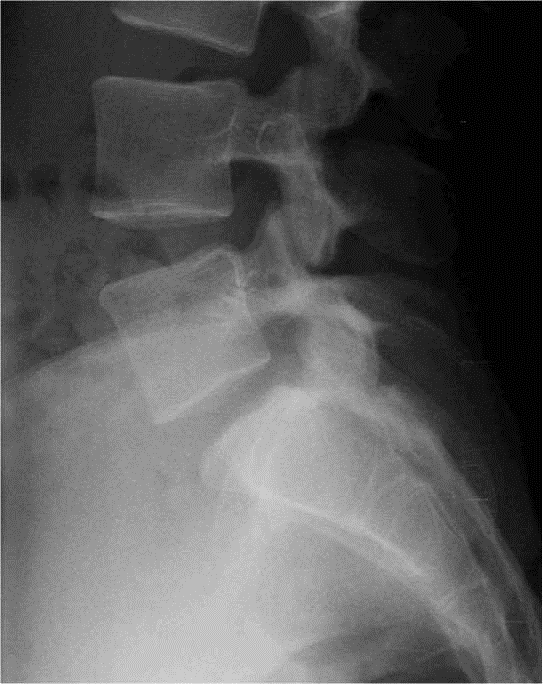

CHARNIERE LOMBO-SACREE

PROFIL

– – Le patient est positionné comme pour une lombaire de profil

RAYON DIRECTEUR

– – Il est centré 2 cm au-dessous de la crête iliaque, sur L5

INTERET

– – Cette incidence permet une mesure de l’angle du bord postérieur de L5 par rapport à l’horizontale : 25 à 30° (+/- 5°)

ANATOMIE RADIOLOGIQUE

- – Corps de L4

- – Corps de L5

- – Pédicule de L5

- – Apophyse de L5

- – Disque L5/S1

IMAGE NORMALE